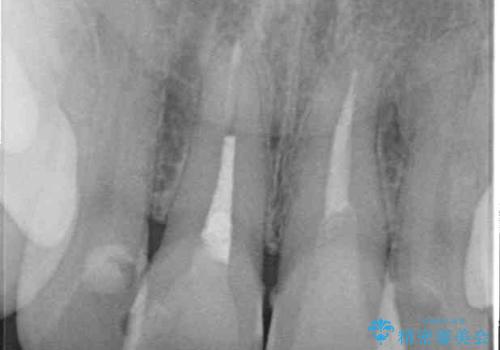

- 変色した前歯2本を気にして来院された患者様です。

右側の前歯は根管治療を行い、その後2本とも歯質に近い素材の土台を植立してオールセラミッククラウンにて補綴することとしました。